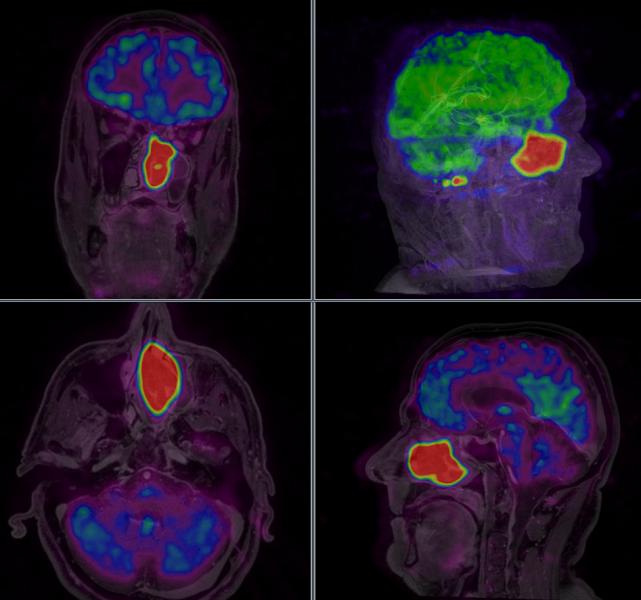

Patterns of brain activity thought to show pain responses have been called into question after researchers saw such patterns in rare patients born without a sense of pain.